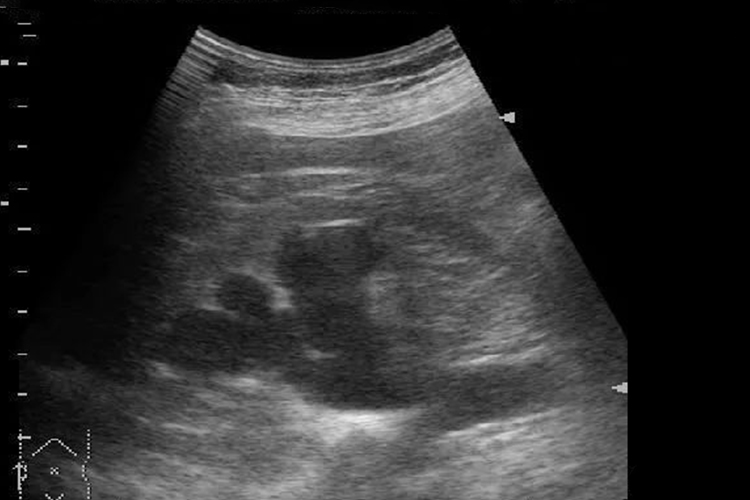

中度肾积水:中度肾积水肾盂、肾盏分离,肾盏扩张较为明显,存在积水的各个肾盏彼此分开,因各人肾盂、肾盏原有形态不同,表现为形态各异的肾积水声像图。例如花朵样或烟斗样无回声区,一般肾实质回声正常。